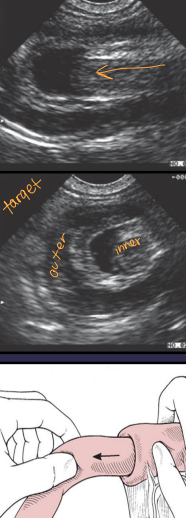

Intussusception

Et: Overlap of junctions of fixed & mobile bowel

Intussusceptum = proximal loop; Intussuscipiens = distal loop

Young: parasites, FB, viral enteritis

Old: neoplasia, infiltrative bowel dz, FB

Cs: diarrhea, anorexia, weight loss, pain

Dt: palpable tubular mass, radiographs (ileus),US

Tx: manual reduction (no adhesions), R&A (devitalized), SURGERY